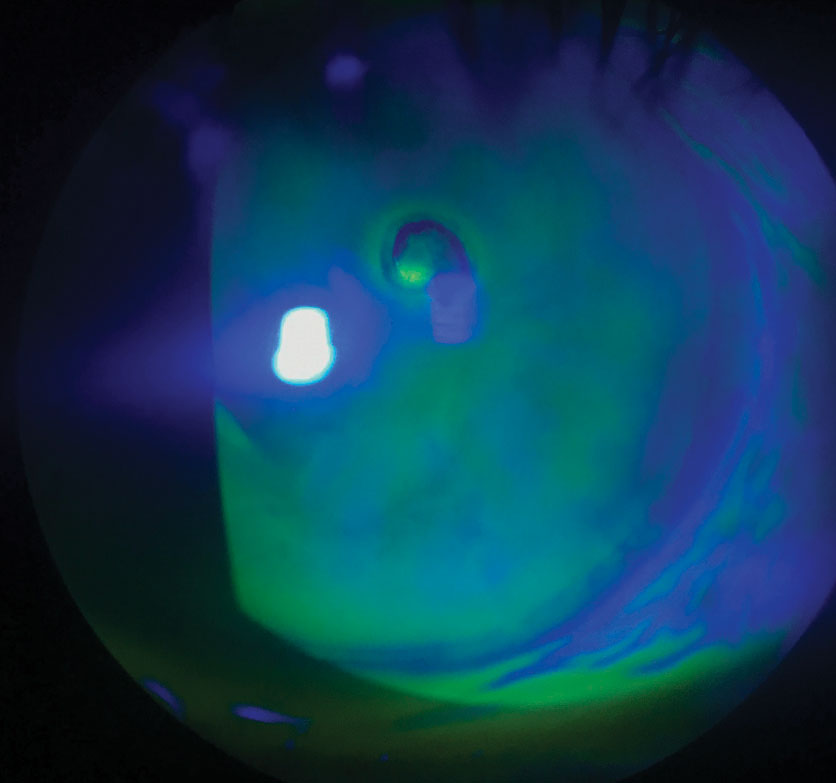

Using a slit lamp microscope, the eye care practitioner examines the corneal layers under high magnification. Eye drops containing green dye called fluorescein are usually instilled to stain the areas of missing epithelium, allowing the eye care practitioner to evaluate the size and depth of the erosion.